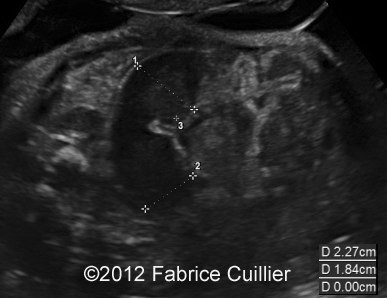

At 32 weeks, the aspect of the intestinal dilatation changed. Low digestive obstruction was suspected (Image 2, 3), with important aggravation at 35 weeks (Image 4). Mesenteric artery and vein had a physiological position (Image 5). Fetal ears and face were normal. Corpus callosus was present (Image 6). The extremities were also normal. Sex was male with bilateral hydrocele (Image 7). Abdominal fetal MRI was performed (Image 8, 9).

Image 2, 3: Slightly intestinal obstruction at 32- 33 weeks.

3A

3B